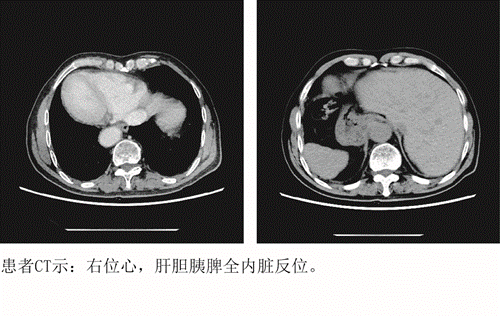

患者周先生,72岁,因“大便性状、习惯改变,便中带血1年”至临床医学院/附属医院就诊,通过肠镜及病理检查显示,为直肠恶性肿瘤;胸、腹部CT显示,全内脏镜面转位。面对如此罕见病例,普外科胃肠外科孙胜主任、宋志主治医师、谈运长主治医师带领团队围绕该患者解剖的变异、术式及围手术期处理进行了细致讨论,制定了严密的手术计划及应急预案。经过充分商讨,决定为患者行腹腔镜下直肠癌根治术,在麻醉科和手术室等全力配合下,经过一个半小时,手术顺利完成。

“镜面人”是完全性内脏反位( situs inversus totalis,SIT)的俗称,是一种罕见的先天性畸形。临床上通常表现为胸腔、腹腔器官及解剖结构的完全左右反位,“镜面人”的发生率约为1/100000,合并直肠癌的“镜面人”则更为罕见。完全性内脏反位通常不影响人的健康,但是一旦患病就会给治疗特别是手术治疗带来巨大障碍。医生的操作习惯和技巧、手术器材等,都是按正常人的内脏方向设计的,如果整个反过来,技术越熟练,甚至还越有可能会犯错,会极大地考验手术医生的专业素养和心理素质。由于手术难度大,常规会较多采用开腹手术,而临床医学院/附属医院采用腹腔镜微创技术为患者实施手术,刚更增大了手术的难度。